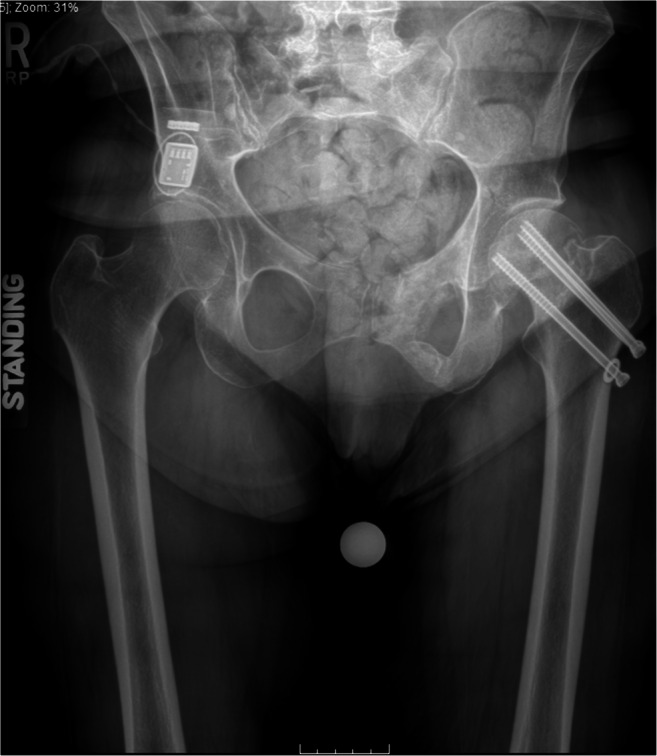

The patient is a 55-year-old female with a longstanding history of bilateral hip pain due to known avascular necrosis. Her right hip was initially more severe both clinically and radiographically, and she underwent elective right total hip replacement prior to the onset of the COVID-19 pandemic. However, in the setting of the COVID-19 elective surgery restrictions, she re-presented to our arthroplasty service with rapid deterioration and intractable pain of the left hip over the previous few weeks. She stated she could not safely transition from a sitting to standing position. Despite attempted use of the walker, she was unable to ambulate, felt unstable on her left side, and stated she was acutely afraid of falling and causing additional injury. She was essentially bedridden due to this clinical deterioration. Radiographic analysis of the left hip demonstrated interval progression of AVN, with collapse of the articulating surface of the femoral head. The collapsed femoral head was now eroding superolaterally through the acetabulum, creating a superolateral rim defect (Fig. 2). Importantly, the patient had no previous medical history that would confer significantly increased risk in the setting of COVID-19, such as heart disease, obesity, diabetes, chronic kidney disease, liver disease, or chronic lung disease.

Fig. 2.

Sequential left hip radiographs demonstrating interval progression of AVN, with collapse of the articulating surface of the femoral head. The collapsed femoral head is now eroding superolaterally through the acetabulum, creating a superolateral rim defect

After presentation of the case to a multidisciplinary peer-review panel at our institution, the unanimous decision was made to proceed urgently with primary THA. It was determined that delay of this surgery could result in continued erosion of the acetabulum, potentially requiring a more challenging and extensive reconstruction and thus conferring additional harm to the patient. Additionally, her rapid clinical deterioration made her a considerable fall risk, and early intervention was felt to be the best option to prevent potential future injury. The patient subsequently underwent uncomplicated direct anterior THA and was discharged home on post-operative day one.